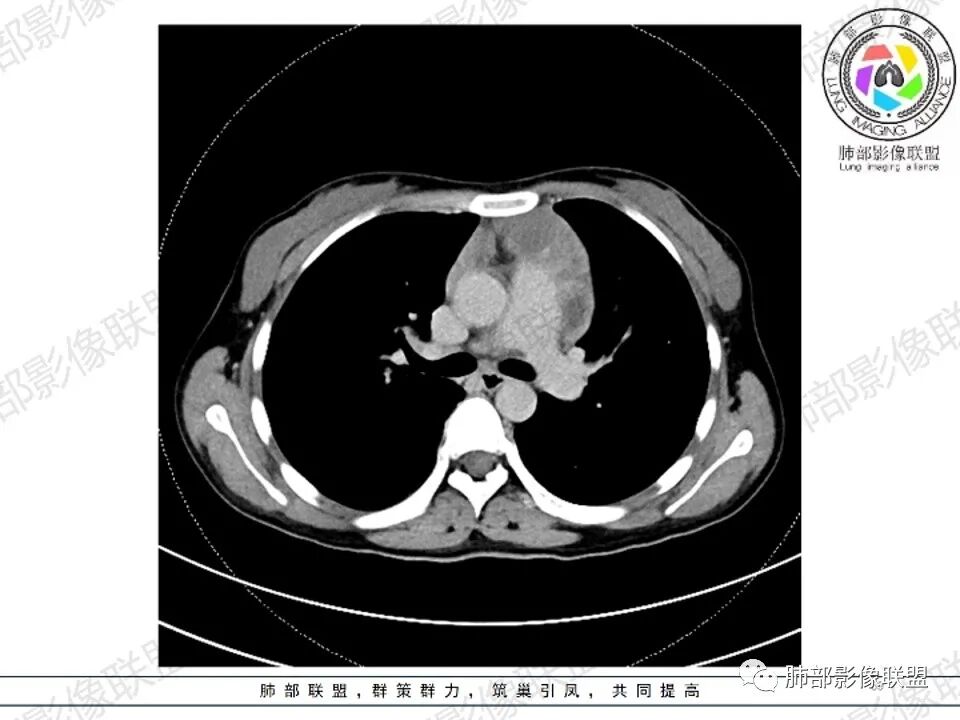

2.影像显示前纵隔不规则块状影,依势贴附心脏大血管旁,密度不均,边界不甚清楚,有结节融合感。

3.病灶轻度不均匀强化,可见血管穿行,散在液性低密度区。

双肺门未见肿大淋巴结。

4.双侧腋窝区见增大淋巴结,边界清楚。